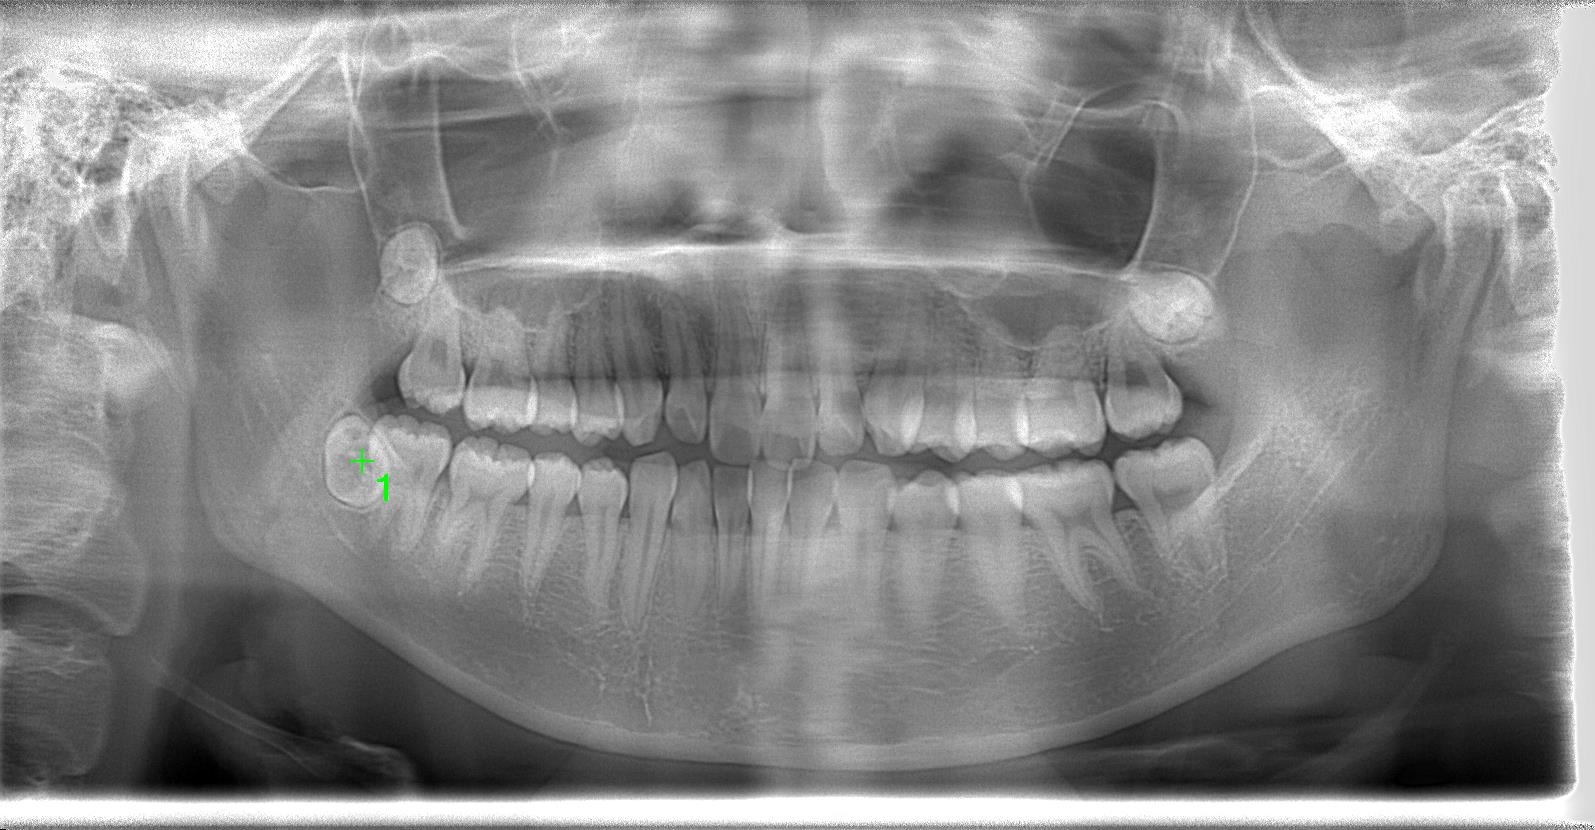

10代後半女性、8埋伏歯の抜歯の難症例

レントゲン写真の状態を御覧ください。

(術前)

部位:右下8番骨性完全埋伏歯